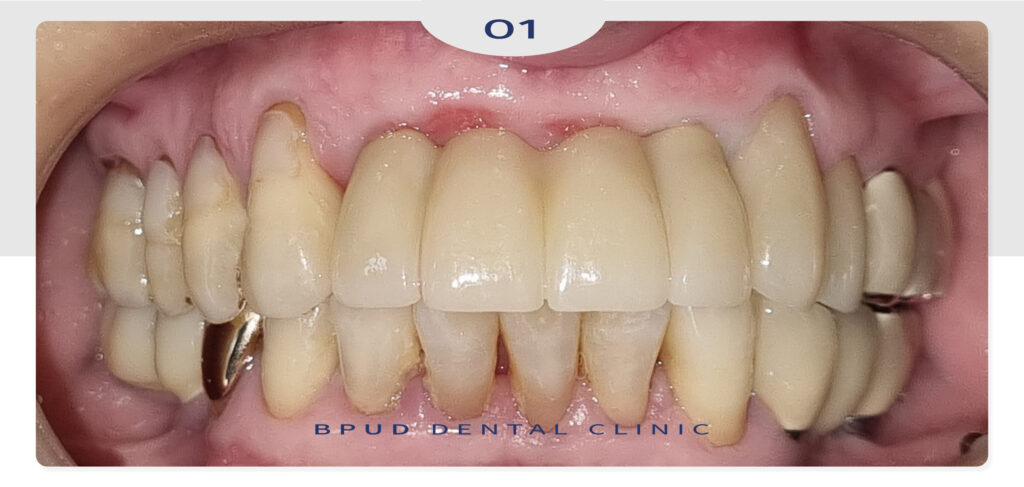

이어서 최종 보철물까지 완료한 모습입니다.

환자분께서도 손상된 치아 뿐만 아니라

기존의 치아까지 치료를 받아 전체적으로

심미적으로 바뀌었다며 매우 만족해 하셨습니다.

앞니는 저작력보다 심미성과 발음, 표현력에

영향을 많이 주는 부위이므로 강한 지지력을

확보하면서도 최대한 자연치와 유사한 형태와

색감을 구현해야 하는데요.